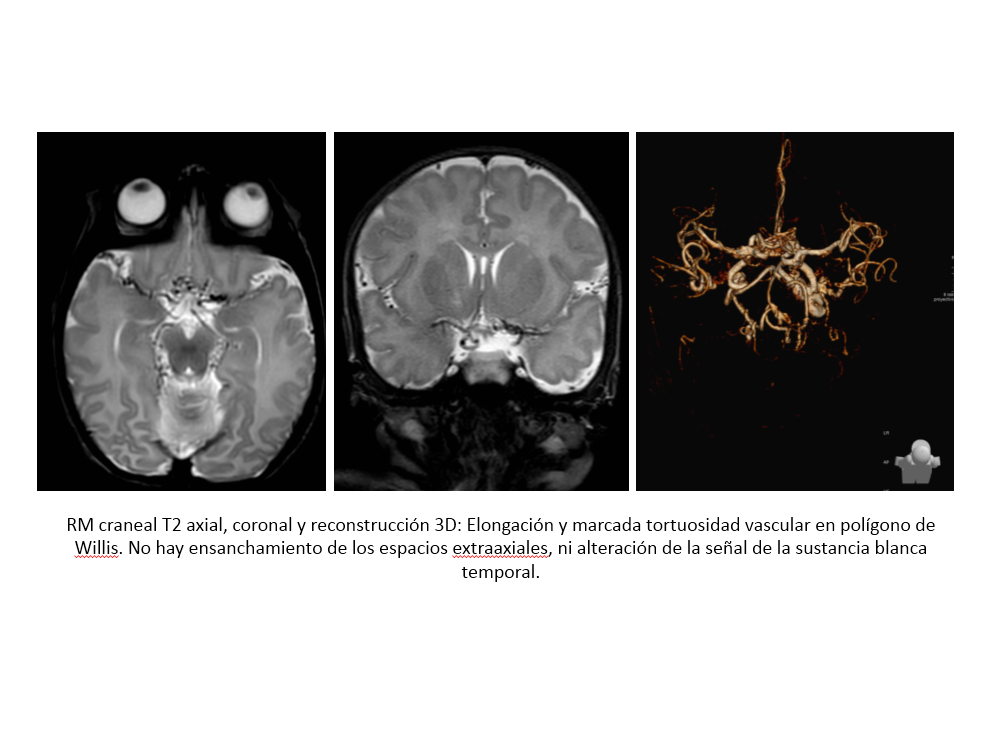

Hallazgos radiológicos: En el cráneo, se aprecian huesos wormianos y en huesos largos, ensanchamiento de las metáfisis, exóstosis y reacción perióstica. En cuanto a los hallazgos en SNC, se puede observar pérdida del volumen cerebral, colecciones subdurales y son característicos los vasos tortuosos y dilatados. En casos avanzados también se puede ver afectación de los ganglios de la base.